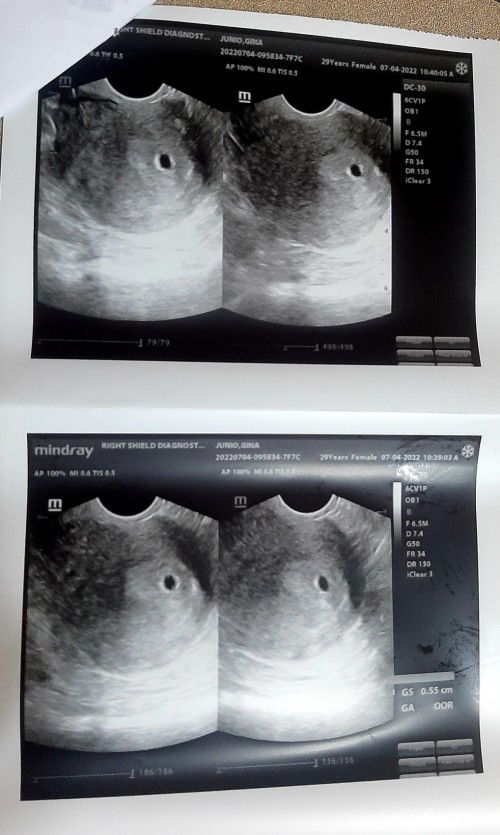

im 4weeks pregnant and my OB prescribed duphaston(pampakapit) is it ok?

Magbasa paSa 15 ko palang po malalaman exact week ko, pero base sa last regla ko 6weeks nako😊😊 ako po Progesterone ung binigay ni ob sken na pampakapit, pinapasok po sa pempem every night.. Tapos nagtetake NG folic at calcium din po☺️☺️ keep safe sting mga soon to be mommies🙏🙏

yan din resita ng ob ko. 6weeks na akong pregnant. pinapasok sa ari apat na tablet sa isang araw

same tayo reseta. 6 weeks and 3 days na ako. 3 times a day sakin pinapatake ni OB.